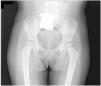

Niña de 2 años que consulta por dolor inespecífico en el miembro inferior izquierdo de un mes de evolución, sin antecedentes personales, familiares o traumáticos de interés. Ni en las analíticas ni en las radiografías (fig. 1) se aprecian signos de infección o de relevancia clínica.

Resonancia magnética de pelvis, con extensa lesión ósea lítica expansiva que afecta el hueso ilíaco, la articulación sacroilíaca y el acetábulo, con disrupción cortical y edema de la musculatura adyacente. Control radiológico a las 6 semanas, con existencia de lesión lítica (flecha) en fase de osificación no visible en el estudio radiológico inicial.

Al tratarse de una lesión unifocal de buen pronóstico1, se inició tratamiento con infiltración de corticoides y restricción de la bipedestación, con mejoría clínica y radiológica significativas (fig. 3).